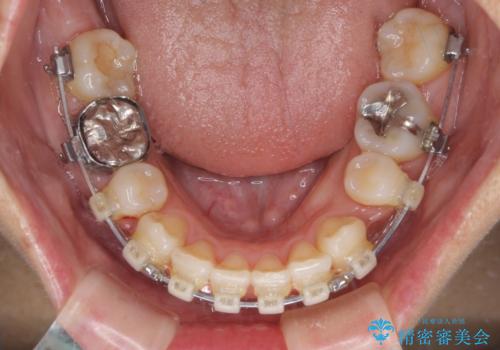

八重歯で口元が膨れている ワイヤー装置での抜歯矯正

- 八重歯と、それによる口元の膨らみを気にして来院された患者様です。

八重歯・デコボコの解消とともに、前方に張り出した上顎前歯を引っ込めることを目的とし、上下左右の第一小臼歯4歯を抜歯をしてワイヤー矯正により治療することとしました。

半年もしないうちに八重歯は解消し、治療も当初予定通り2年強で終えることができました。